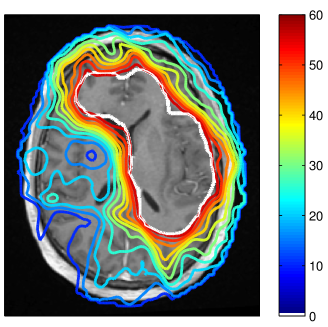

Refer to caption

Figure 3: Simulated tumor cell density based on the segmentation in figure 2 for parameters λw=4.2subscript𝜆𝑤4.2\lambda_{w}=4.2 mm and Dw/Dg=100subscript𝐷𝑤subscript𝐷𝑔100D_{w}/D_{g}=100 (a) and Dw/Dg=10subscript𝐷𝑤subscript𝐷𝑔10D_{w}/D_{g}=10 (b) . The color scale refers to the log10𝑙𝑜subscript𝑔10log_{10} cell density normalized to the carrying capacity.

In this paper, we are concerned with the spatial definition of the target volume as an isoline of the tumor cell density. In that context, the exact value of the infiltration length λwsubscript𝜆𝑤\lambda_{w} is irrelevant because it does not affect the shape of the isolines. Only the abolute values of the tumor cell density associated with the isolines are determined by λwsubscript𝜆𝑤\lambda_{w} 333The value of λwsubscript𝜆𝑤\lambda_{w} will be crucial for dose prescription considered in the accompanying paper [16].. Thus, the only relevant model parameter for this paper is the ratio Dw/Dgsubscript𝐷𝑤subscript𝐷𝑔D_{w}/D_{g}, which determines the shape of the isolines of the cell density together with the brain segmentation. The literature consistently suggests that tumor cells infiltrate gray matter much less than white matter444This holds for the most common case of astrocytomas, not necessarily for oligodentrogliomas (see [12] for a review of glioma growth patterns). This suggests a large value for Dw/Dg1much-greater-thansubscript𝐷𝑤subscript𝐷𝑔1D_{w}/D_{g}\gg 1. Most illustrations in this paper were obtained for Dw/Dg=100subscript𝐷𝑤subscript𝐷𝑔100D_{w}/D_{g}=100. The most appropriate value is however uncertain and we discuss the impact of uncertainties in Dw/Dgsubscript𝐷𝑤subscript𝐷𝑔D_{w}/D_{g} in section 3.5.

In addition to the segmentation, the ratio of white and gray matter diffusion coefficient Dw/Dgsubscript𝐷𝑤subscript𝐷𝑔D_{w}/D_{g} influences the shape of the isolines of the tumor cell density. For Dg=0subscript𝐷𝑔0D_{g}=0, gray matter represents a hard boundary and tumor cells only spread in white matter. For Dw/Dg=1subscript𝐷𝑤subscript𝐷𝑔1D_{w}/D_{g}=1, tumor cells spread equally in white and gray matter and the shape of the target is solely influenced by anatomical constraints. In figure 3 the simulated tumor cell density is compared for Dw/Dg=10subscript𝐷𝑤subscript𝐷𝑔10D_{w}/D_{g}=10 and Dw/Dg=100subscript𝐷𝑤subscript𝐷𝑔100D_{w}/D_{g}=100. For smaller Dw/Dgsubscript𝐷𝑤subscript𝐷𝑔D_{w}/D_{g}, the cell density is more washed out (figure 3b) compared to a larger Dw/Dgsubscript𝐷𝑤subscript𝐷𝑔D_{w}/D_{g} where the tumor cell density follows more closely the white matter structure (figure 3a). It has been discussed above that the cortical gray matter has a thickness of only a few millimeters. As a consequence, varying Dw/Dgsubscript𝐷𝑤subscript𝐷𝑔D_{w}/D_{g} has little impact on the global shape of the target volume. The most significant changes for this patient are around the lateral sulcus.